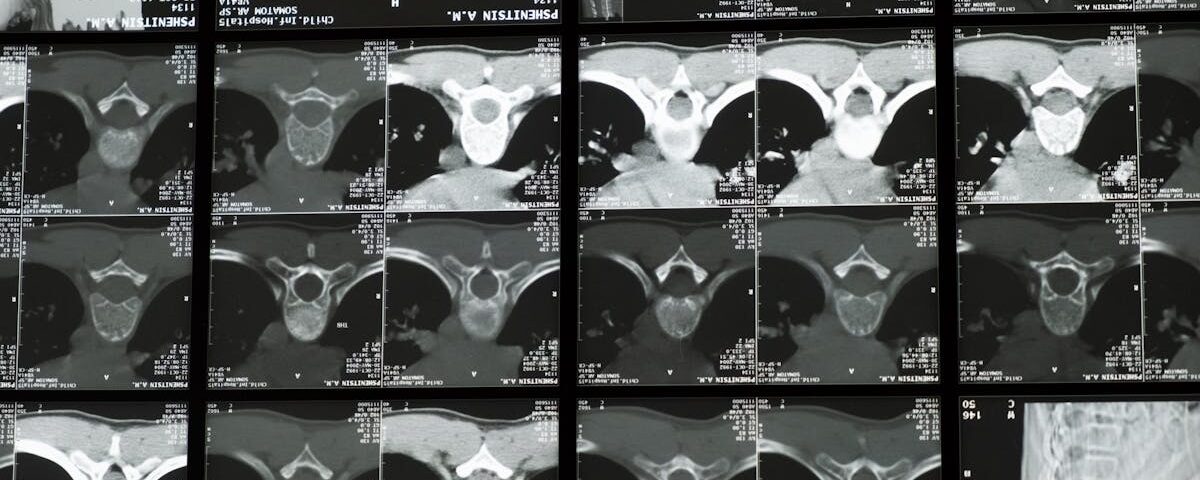

Un examen clinique, combiné à une imagerie médicale comme une IRM, est nécessaire pour un diagnostic précis.